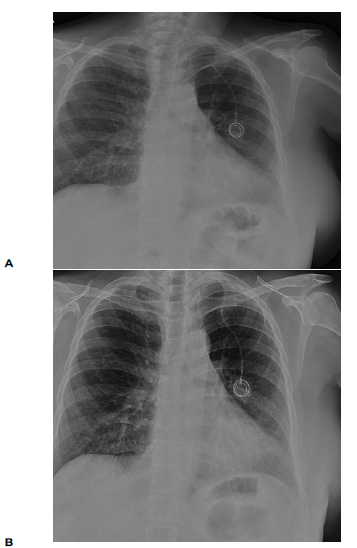

During routine follow-up, a thoracic CT was requested in January 2025 (Figure 1), which revealed a fracture at the upper portion and displacement of the catheter, with an approximately 11 cm fragment lodged in the right atrium and ventricle. This was an incidental finding. The scan also showed scattered micronodules and fibrotic changes in the lung parenchyma.

Figure 1

High-resolution chest CT scans showing the reservoir catheter in the right atrium and ventricle. A) Transverse view; B) Sagittal view.

Source: SOLCA Hospital-Guayaquil.